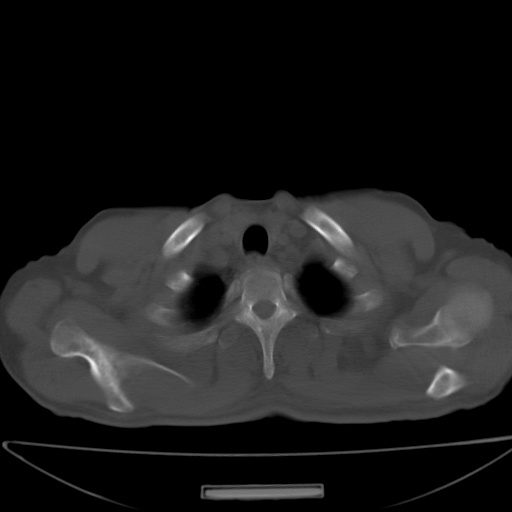

以下是引用jsgdoctor在2008-11-6 22:12:00的发言:[br]右主支气管壁明显增厚,管腔狭窄.考虑为右侧中央型肺癌伴阻塞性炎症\\肺脓肿.

以下是引用zjzjr在2008-11-6 20:25:00的发言:[br]中心型肺ca,合并阻塞性肺炎

以下是引用zsl6918在2008-11-6 19:43:00的发言:[br]右侧中心性肺癌(鳞癌)